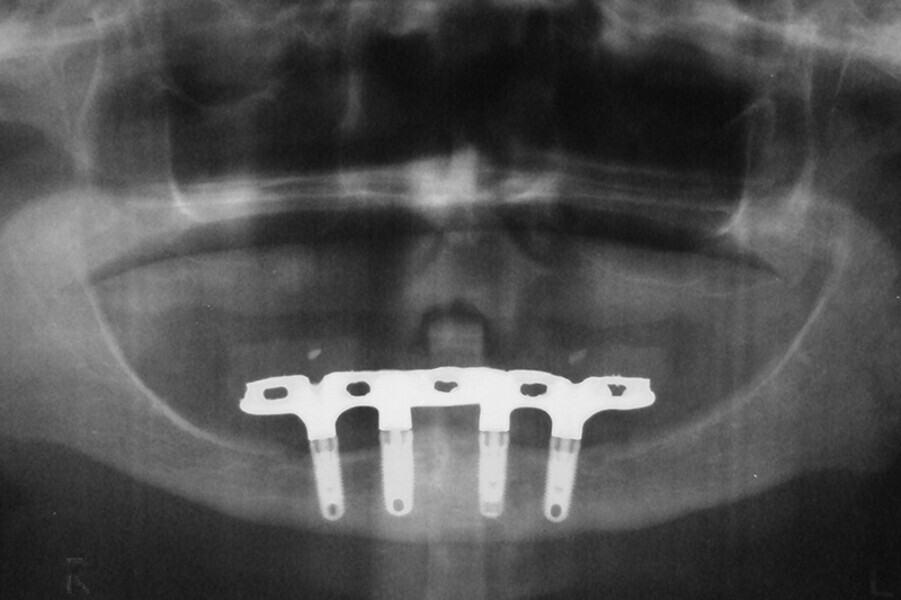

Fig. 7. Rx Pre-operatoria, Prótesis híbrida inmediata con 10 años de evolución y Rx Control a los 10 años.